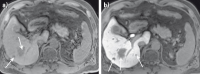

MRT-Diagnostik

Abbildung 1a-b: MRT-Kontrastmittel zur Differenzierung zwischen Leberzyste und Hämangiom. (a) T2-gewichtetes Bild zeigt 2 ähnlich erscheinende helle oder hyperintense Läsionen im Segment 6 des rechten Leberlappens (Pfeil und Pfeilspitze). Eine Differenzierung zwischen beiden Läsionen ist nicht möglich. (b) In dem T1-gewichteten Bild nach KM-Gabe zeigt das Hämangiom (Pfeil) eine kontinuierliche KM-Aufnahme von der arteriellen zur Äquilibriumphase (so genanntes „Pooling“), wobei die Zyste keine KM-Aufnahme aufweist und daher dünkler als das Lebergewebe ist.